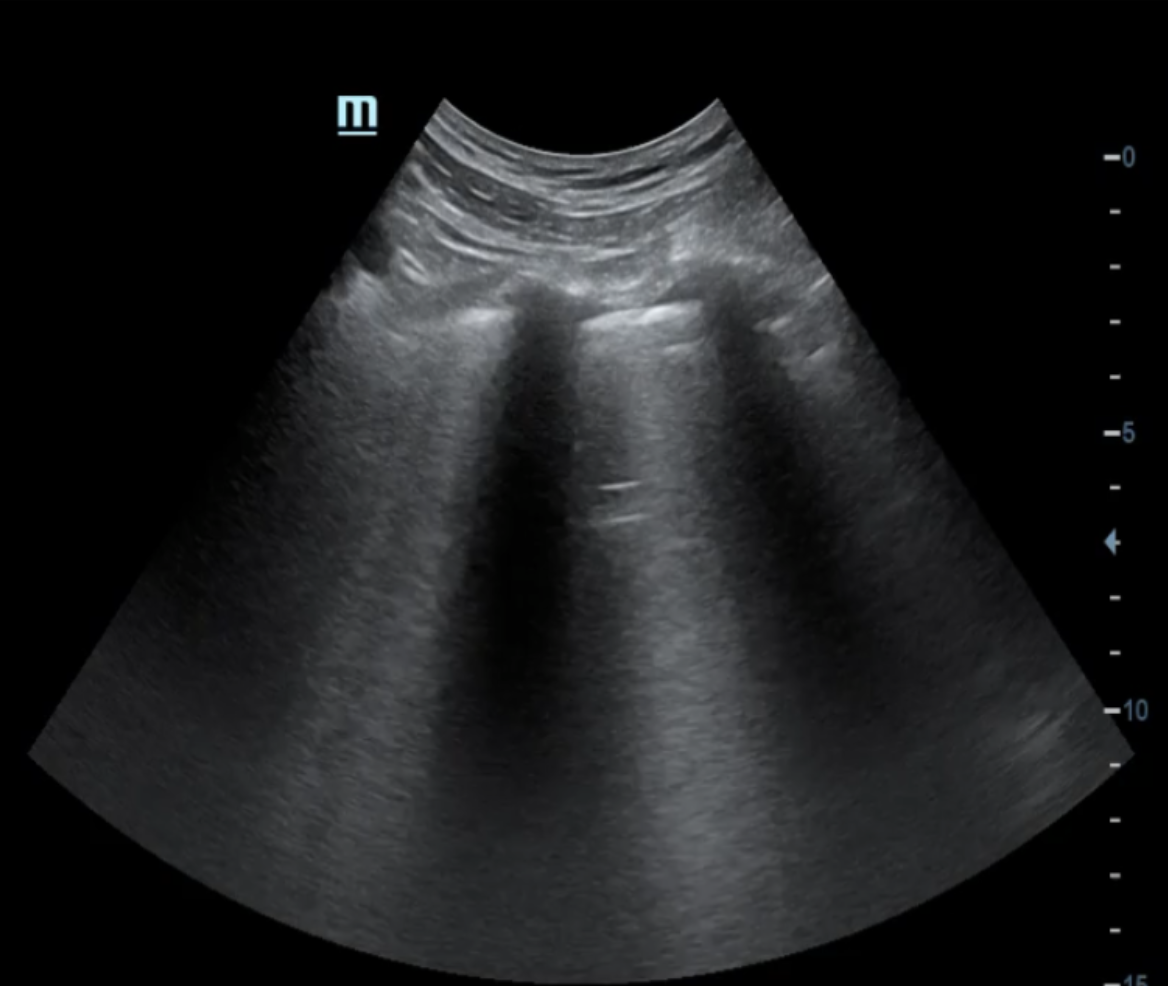

Descripción de los hallazgos ecográficos y las imágenes más relevantes para la resolución del caso

A la exploración ecográfica pulmonar se objetivan líneas B en ambos campos anteriores y superiores, así como derrame pleural bilateral, orientando la causa de la disnea hacia la insuficiencia cardíaca.

A posteriori en consulta se realiza ecografía de control donde se observa la desaparición de líneas B y resolución del derrame pleural bilateral.